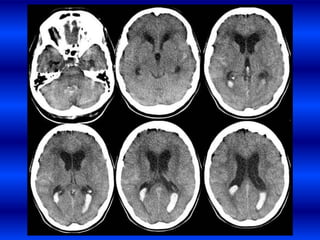

INFARTOS SUBCLÍNICOS

Los estudios poblacionales han demostrado que los infartos subclínicos

incrementan 2-4 veces el riesgo de infarto clínico

• Estudios poblacionales usando RMN han

demostrado que el 8-28 % de los adultos

tienen evidencias de infartos silentes.

• Imagen hipointensa en T1 3 mm.

• Si se suman los infartos silentes a los

infartos clínicos, la prevalencia de ECV se

incrementa a aproximadamente 20 % de la

población.

Infarto cerebral silente. •Una gran parte de los enfermos tienen dificultades cognitivas, de la marcha u otros síntomas que por ser ligeros pueden no reconocerse INFARTOS SUBCLÍNICOS Los estudios poblacionales han demostrado que los infartos subclínicos incrementan 2-4 veces el riesgo de infarto clínico

• 24.

• Estudios poblacionalesusando RMN han demostrado que el 8-28 % de los adultos tienen evidencias de infartos silentes. • Imagen hipointensa en T1 3 mm. • Si se suman los infartos silentes a los infartos clínicos, la prevalencia de ECV se incrementa a aproximadamente 20 % de la población.